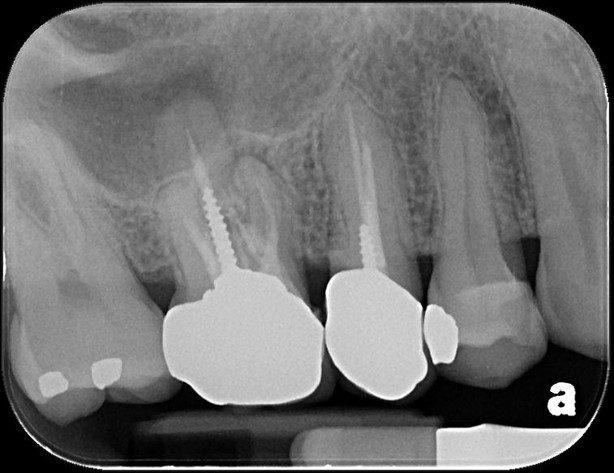

治療前,第一大臼齒根尖病變

顯微根管重治療